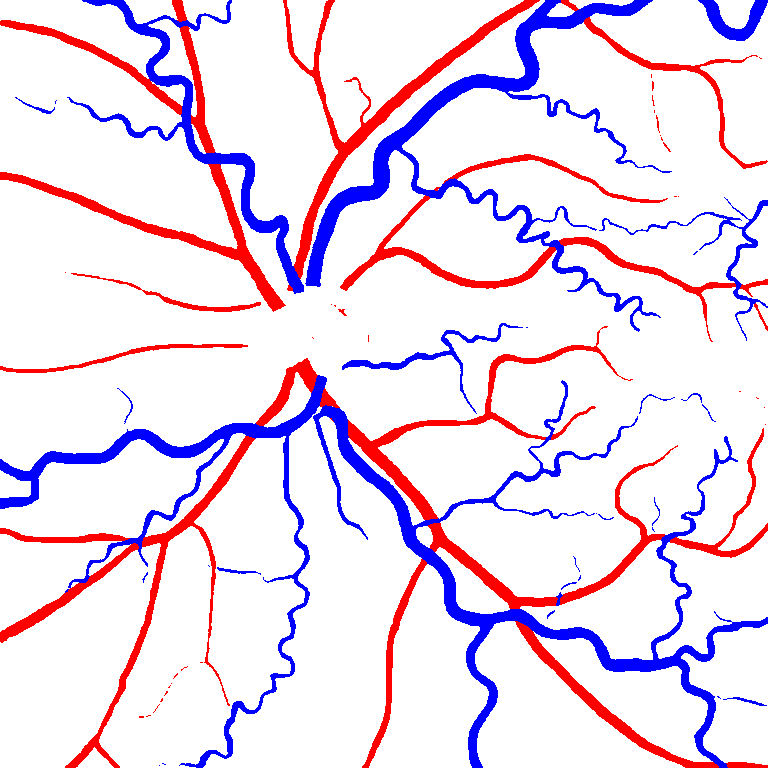

Using the final pretrained student SegRAVIR model in our knowledge distillation framework described in Section IV-D, we fine-tuned and tested the network on three publicly available datasets of color images, DRIVE [10], STARE [9], and CHASE_DB1 [12]. Fig. 7 shows example of SegRAVIR segmentation outputs on DRIVE and CHASE_DB1 datasets. Table VII presents a quantitative comparison between the segmentation performance of our SegRAVIR model and state-of-the-art models: R2U-Net [25], DU-Net [26], and IterNet [34]. By all evaluation metrics, SegRAVIR has achieved new state-of-the-art results on the DRIVE, STARE [9], and CHASE_DB1 datasets.